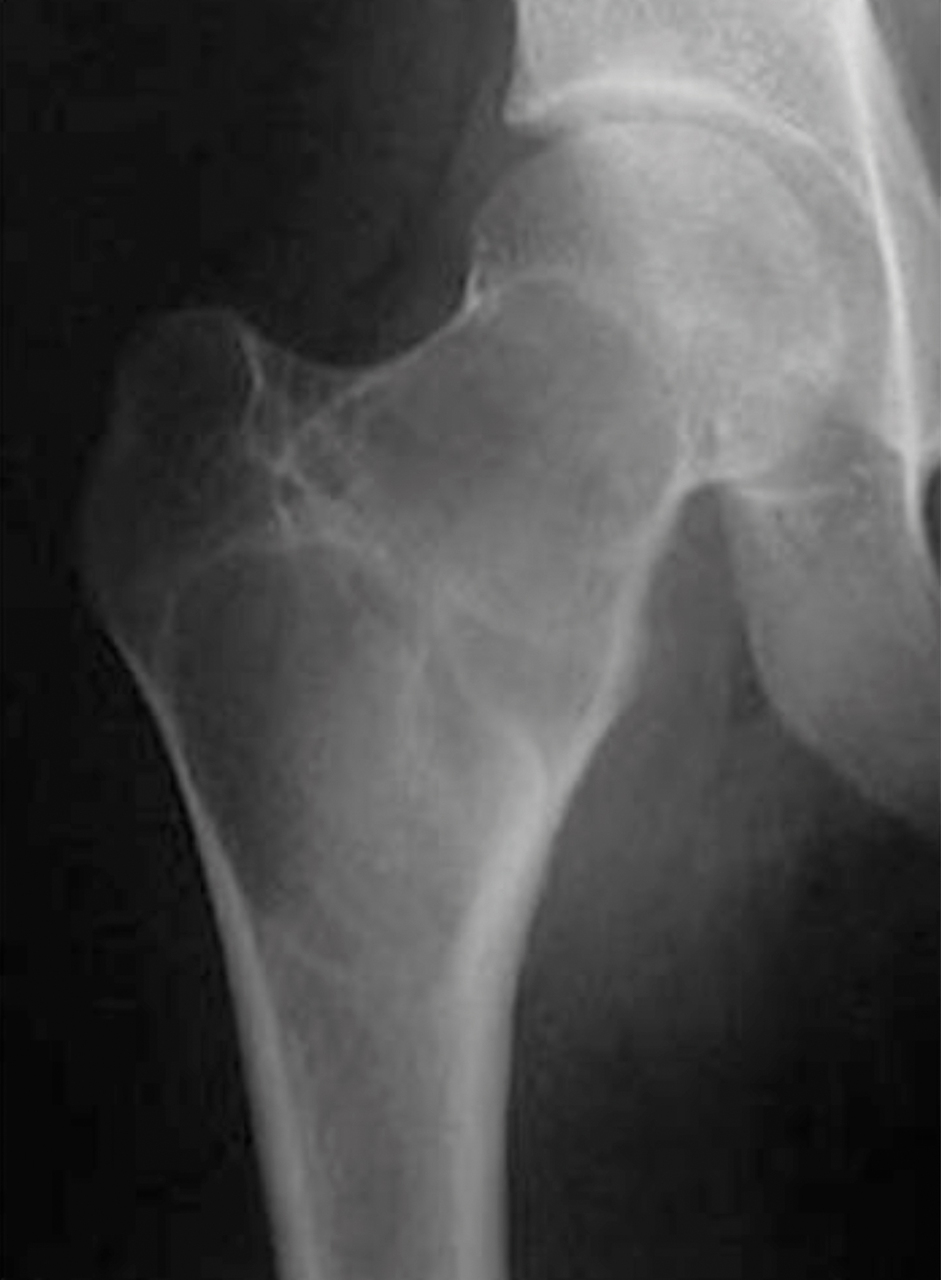

Quel est votre diagnostic ?

Il s'agit d'un processus lytique au sein de la métaphyse fémorale supérieure. La lyse est cernée d'une sclérose périphérique régulière. Elle contient quelques travées qui sont régulières et respectées. L'ensemble dessinant un "contour géographique". Les corticales sont discrètement déformées et amincies, mais également de façon régulière, sans effraction. Il n'y a pas de réaction périostée. Il n'y a pas d'expansion apparente dans les parties molles. Cet aspect radiologique est calme, traduisant plutôt une tumeur bénigne. Ce processus est lent. Il reste donc régulier, souvent cerné d'une bande de sclérose qui est une construction réactionnelle de l'organisation, mais qui dans ce cas est bien limitée et respectée.